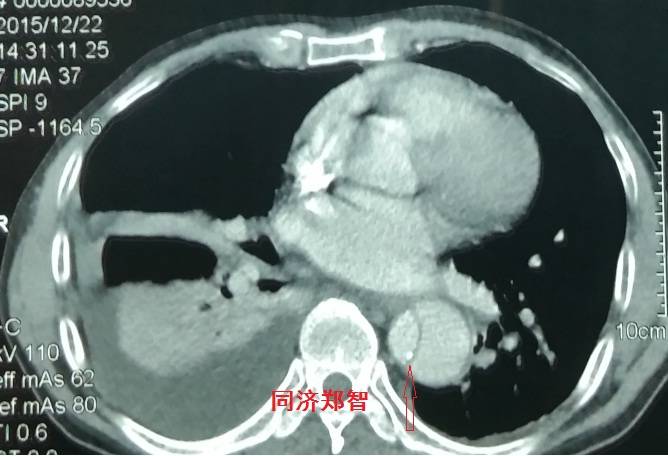

病例三

胸部平扫CT提示胸降动脉增宽(红色星形标记),CTA证实B型主动脉夹层伴降主动脉夹层动脉瘤形成。